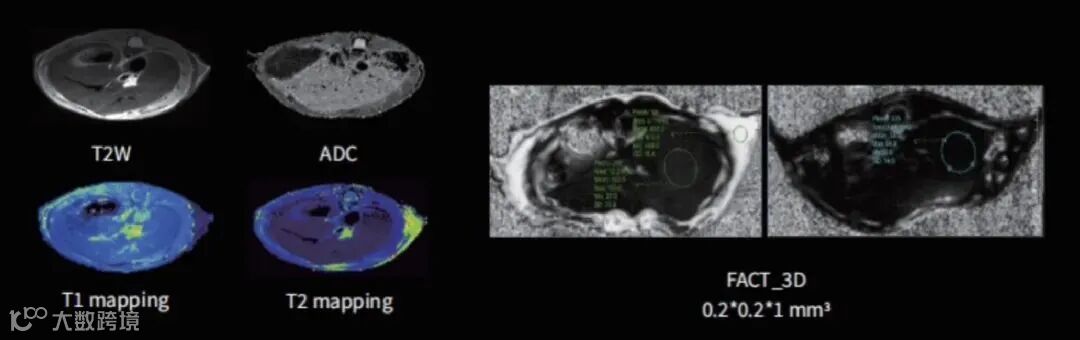

利用其高分辨率和软组织对比度优势,核磁共振能够精确检测和分析小动物腹部器官的细微病变。可通过T2W、ADC、T1/T2 mapping、FACT_3D等技术成像(如图9),观察组织器官形态,评估组织微观结构,为疾病模型研究和药物测试提供重要数据。

图9 不同序列下腹部组织成像